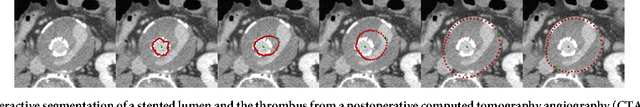

In this contribution, a semi-automatic segmentation algorithm for (medical) image analysis is presented. More precise, the approach belongs to the category of interactive contouring algorithms, which provide real-time feedback of the segmentation result. However, even with interactive real-time contouring approaches there are always cases where the user cannot find a satisfying segmentation, e.g. due to homogeneous appearances between the object and the background, or noise inside the object. For these difficult cases the algorithm still needs additional user support. However, this additional user support should be intuitive and rapid integrated into the segmentation process, without breaking the interactive real-time segmentation feedback. I propose a solution where the user can support the algorithm by an easy and fast placement of one or more seed points to guide the algorithm to a satisfying segmentation result also in difficult cases. These additional seed(s) restrict(s) the calculation of the segmentation for the algorithm, but at the same time, still enable to continue with the interactive real-time feedback segmentation. For a practical and genuine application in translational science, the approach has been tested on medical data from the clinical routine in 2D and 3D.